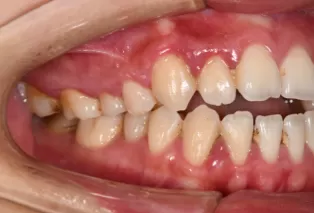

Intraoral photos